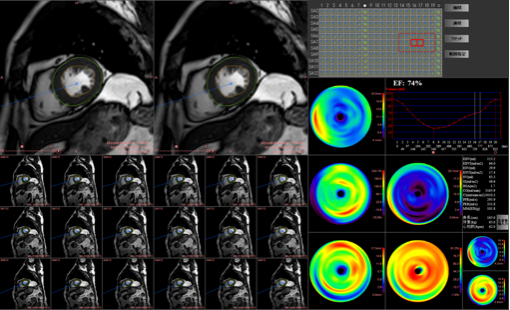

3テスラのMRI装置は、従来の1.5テスラと比較し高い信号が得られるため、空間解像度や画像コントラストが向上します。また、新たな高速撮像技術であるcompressed SENSEによって、画質を維持したままで大幅な撮像時間の短縮が可能となっています。これらの技術は、当院で行なっている心臓領域での有用性も高く、画質向上および検査時間短縮に寄与しています。

非造影心臓MRI

腎臓の機能が低い場合には、造影剤を用いる冠動脈CT検査は出来ません。MRIでは、造影剤を使用しなくても冠動脈や心臓の機能、心筋の性状を評価する事ができます。

急性心筋梗塞の1例:シネMRI画像(左から中央)では、左心室の一部で収縮が低下している領域があり、心筋の浮腫(T2)画像では、同部位に信号値の高い部分を認め、急性心筋梗塞の所見となります。

造影心臓MRI